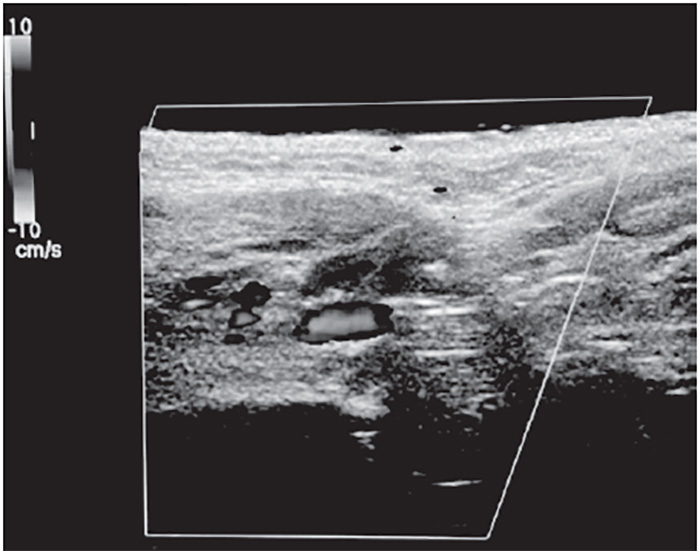

The superficial temporal artery is a branch of the external carotid artery and divides into frontal and parietal branches at the cranial portion of the zygomatic arch. The parietal branch is more medial and superficial to the temporal fascia, overlying the temporalis muscle, and must be avoided [131]. Inadvertent direct injection and/or compressive ischemia can cause retrograde embolization of the ophthalmic artery and blindness [132]. The superficial temporal artery must be carefully palpated and marked; cannula placement should be medial when placing polydioxanone (PDO) threads for midface lifts. The superficial temporal artery is visible with color Doppler ultrasound, when performed with proper technique (Figure 6).

The facial artery is a branch of the external carotid artery, emerging superficial to the posterior belly of the digastric muscle, stylohyoid muscle, and submandibular gland, and coursing in a continuous oblique plane (1.5 cm)from the lateral commissure of the mouth to nasal ala along the lateral border of the nasolabial fold [146]. Proper injection technique for injecting cosmetic filler to the nasolabial fold is medial and very superficial, targeting the lower two-thirds intradermal plane, avoiding the nasal ala, where facial artery is most superficial [147].Inadvertent direct subcutaneous intravascular facial artery injection and/or compressive ischemia in the upper third of the nasolabial fold can result in an ocular embolism, blindness, and necrosis of the alar and malar region of the nose and cheek [148]. The facial artery is visible with color Doppler ultrasound when using proper technique (Figure 9).

The submental artery branch of the facial artery is seen in the inferior border of the mandible within the retromandibular groove at the mandibular notch, superficial to the mylohyoid muscle, and oriented in the long axis of the body of the mandible [31]. Avoid direct injections in the area of the retromandibular groove when applying local anesthesia to cheek and jawline [50]. The submental artery is visible with color Doppler ultrasound (Figure 11).